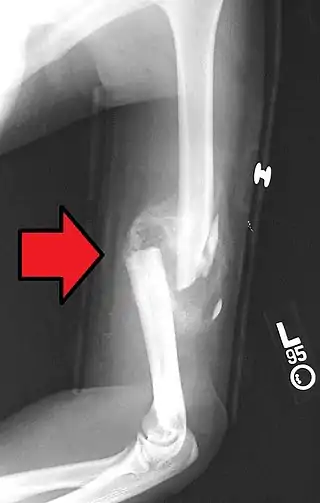

Fracturas diafisarias del húmero

La diáfisis del húmero es el segmento largo del hueso y suele fracturarse en la inmensa mayoría de los casos en adultos que, en plena actividad y como consecuencia de acciones violentas, aplican golpes contusos o penetrantes directamente sobre el brazo. Algunas de las causas de este tipo de fractura incluyen caídas de motocicleta y otros accidentes viales, arrollamientos, caídas de caballos, caídas de patines, etc. Las fracturas diafisarias del húmero ocurren en pacientes con edad promedio de 55 años y representan cerca del 1% de todos los casos de fracturas.[2] Por lo violento que suele ser el golpe, la fractura de la diáfisis del húmero tiende a acompañarse con lesiones secundarias al nervio radial y, con menos frecuencia, a la arteria humeral.